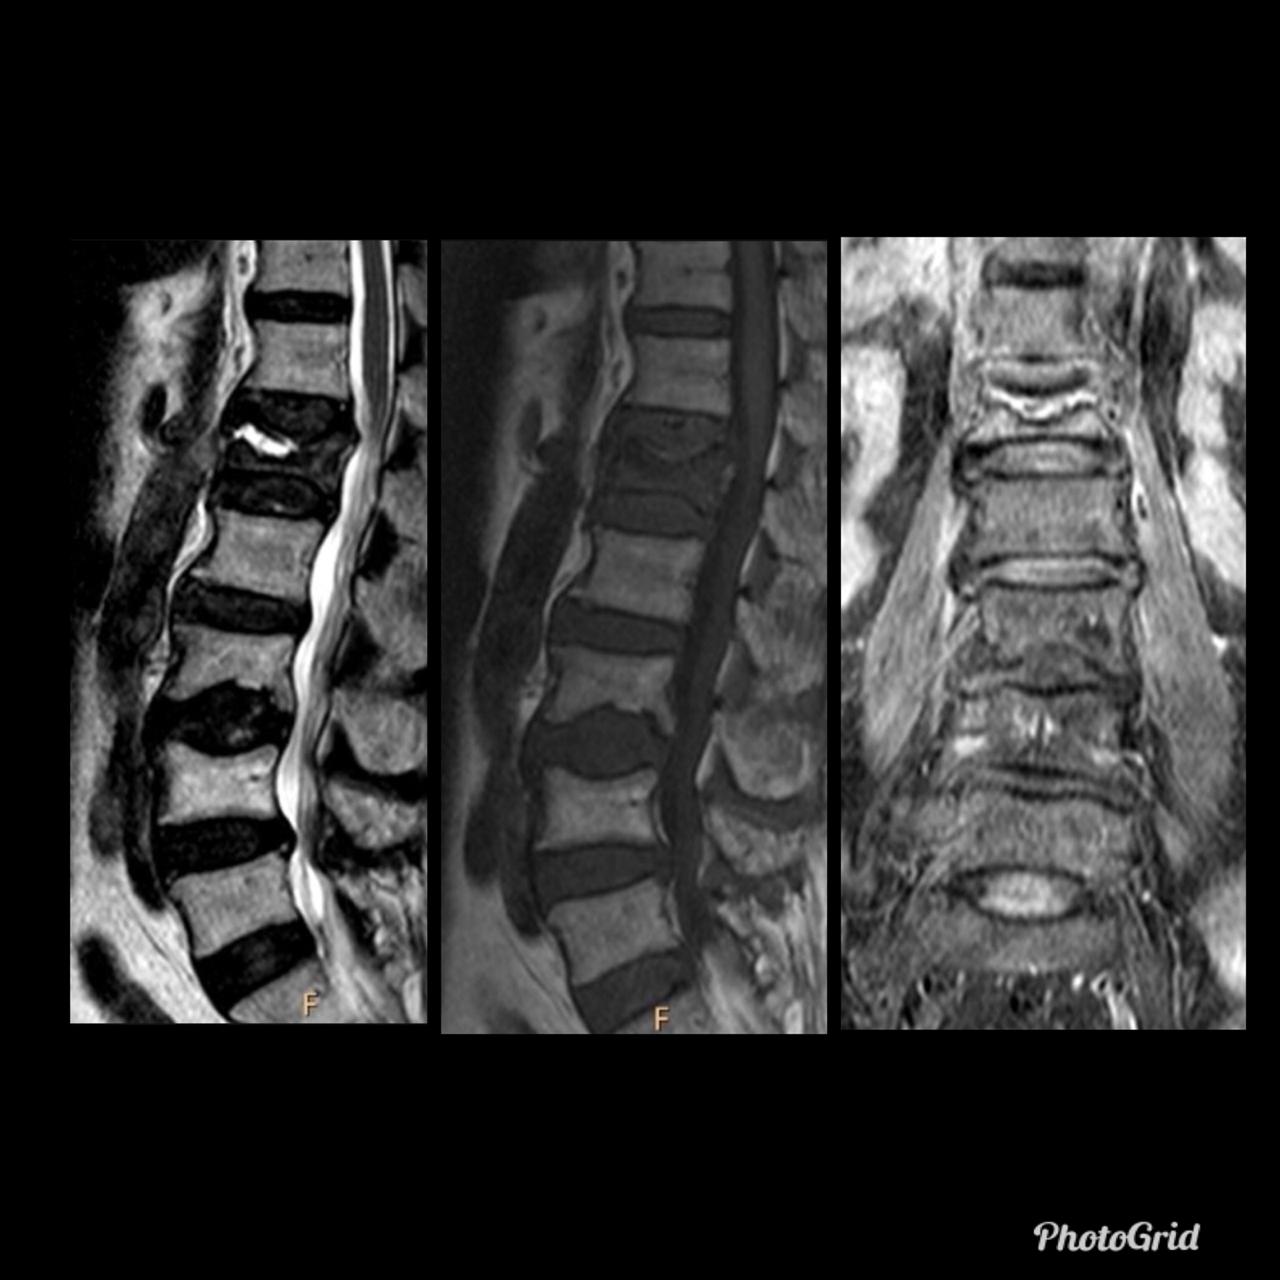

In fractured vertebral bodies, the fluid sign was adjacent to the fractured end plates and exhibited signal intensity isointense to that of cerebrospinal fluid on a background of diffuse hyperintensity in the vertebral body because of acute collapse.

It is seen in acute vertebral compression fractures that show bone marrow edema. In osteoporotic fractures, the fluid sign was significantly associated with fracture severity.